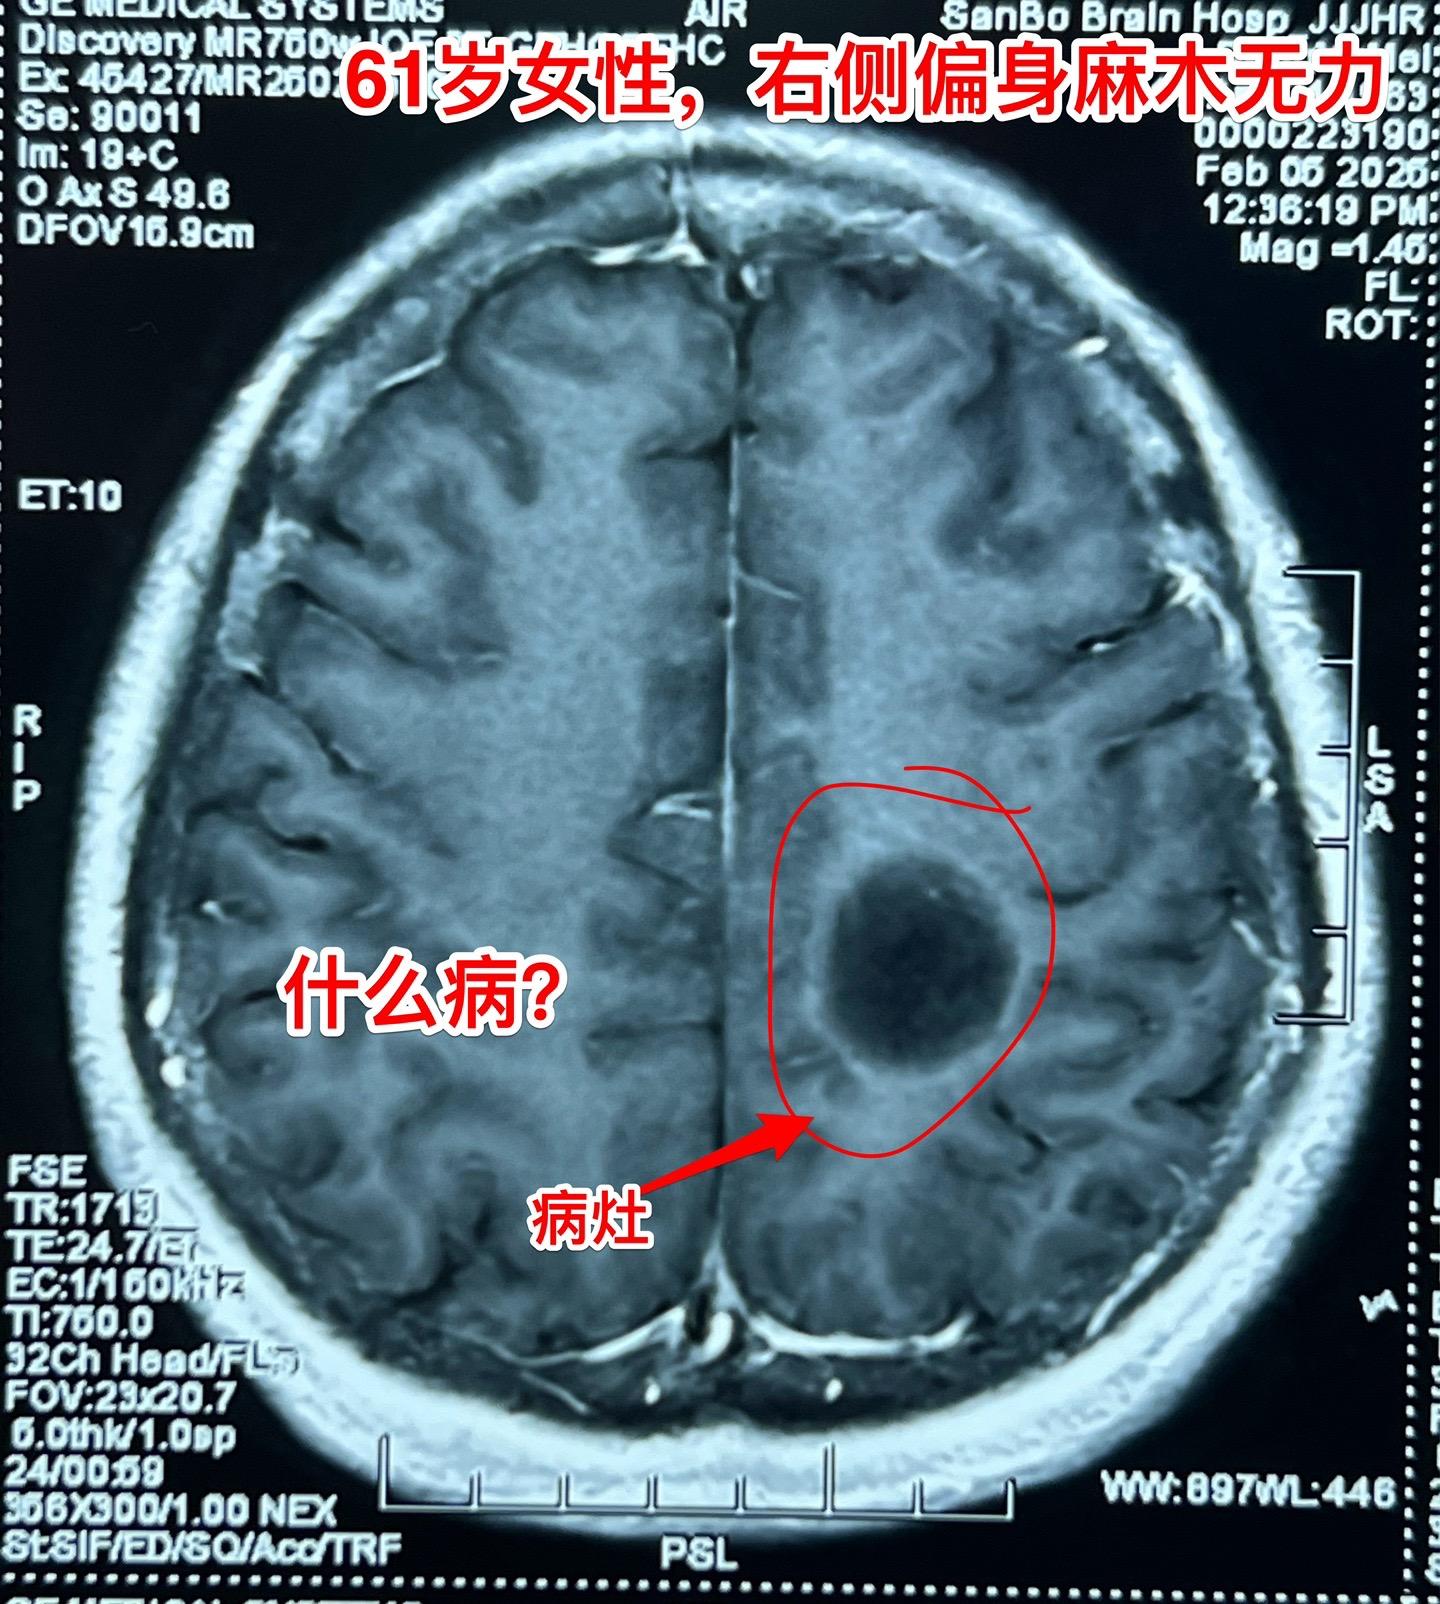

疾病多种多样,鉴别诊断不易!近几年人工智能AI发展迅猛,成果惊人! 听说有AI医院! 医生和病人都会提问:AI能取代医生看病吗? 今天介绍一个病人,61岁女性,因右侧偏身麻木无力来看病。CT和磁共振显示左侧中央区有个病灶,见图。怀疑是胶质瘤? 病人的症状越来越严重,正月初九住院后行走困难,而且右手手指难以张开,术前和病人家属充分交流、沟通,这个位置属于中央区,手术后很可能症状会加重。患者的两个儿子均想积极治疗。住院后两天做了手术。手术过程中发现